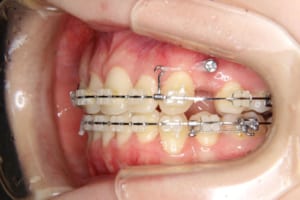

治療中

使用した装置 マルチブラケット装置(唇側矯正)

InVuブラケット

シルバーワイヤー

ホールディングアーチ

歯科矯正用アンカースクリュー(1本)

その他/備考 上顎右側中切歯および側切歯が、埋伏していた犬歯によって歯根吸収していました。

牽引に半年かかりました。

顎間ゴムも頑張ってくれたが期間がかかりました。